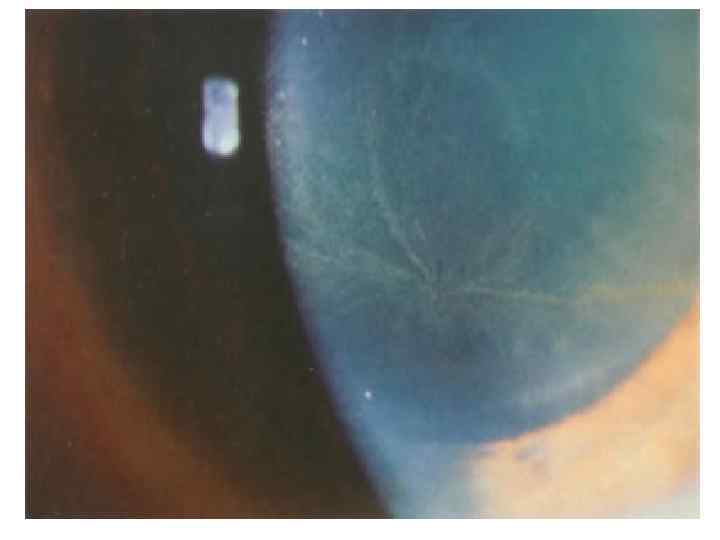

Клиническая картина • Жалобы: 1. Боль – наиболее ранний симптом! Выделяют два основных типа болей: Нейропатическая боль (акропарестезии). Постоянное жжение и покалывание, ощущение дискомфорта. Эта боль обычно затрагивает ступни и ладони. Кризы Фабри. Возникающие время от времени сильная, жгучая боль, возникающие в ступнях или ладонях и иногда распространяющиеся на другие части тела. Эта боль может быть весьма изнуряющей и продолжаться от нескольких минут до нескольких дней. 2. Нарушение потоотделения. 3. Быстрая утомляемость и непереносимость физических нагрузок. 4. Ангиокератомы - мелкие, красновато-фиолетовые безболезненные папулы на коже. С возрастом количество ангиокератом у больных увеличивается, также иногда увеличиваются размеры отдельных элементов сыпи (до 10 мм). Наиболее часто ангиокератомы располагаются в области губ, пальцев рук и ног, ано-генитальной области (при достижении половой зрелости).